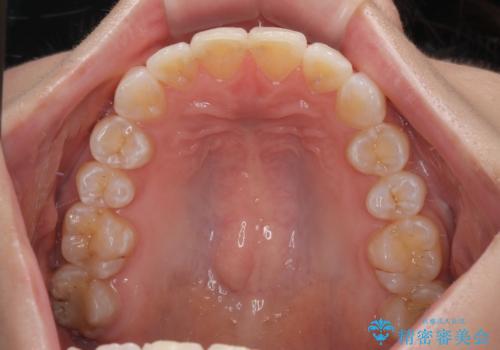

- 上下前歯のデコボコとディープバイトを気にして来院された患者様です。

歯列全体に叢生があり、舌の突出癖が認められたため、突出癖が改善されない場合には口元が突出するリスクが考えられました。

マウスピースでもワイヤーでも対応可能でしたが、煩わしいことは避けたいとのことで、舌のトレーニングをしっかりと行っていただきながら、ワイヤー装置にて矯正治療を行うこととしました。